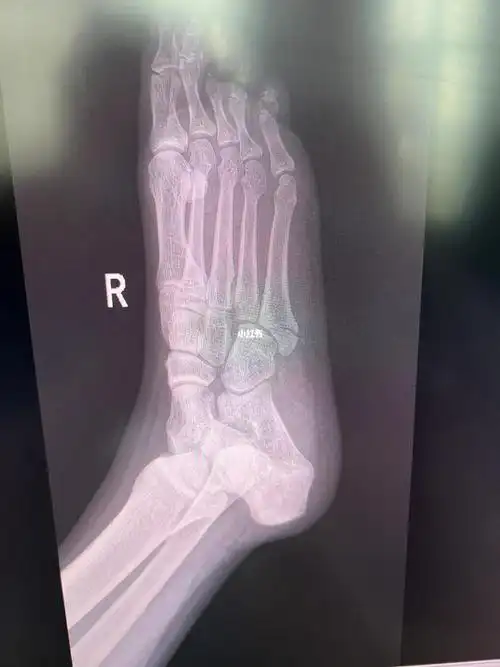

术后42天 满六周了 骨折45天

脚踝骨折保守治疗第58天拍的片与44天比较

第五跖骨骨折